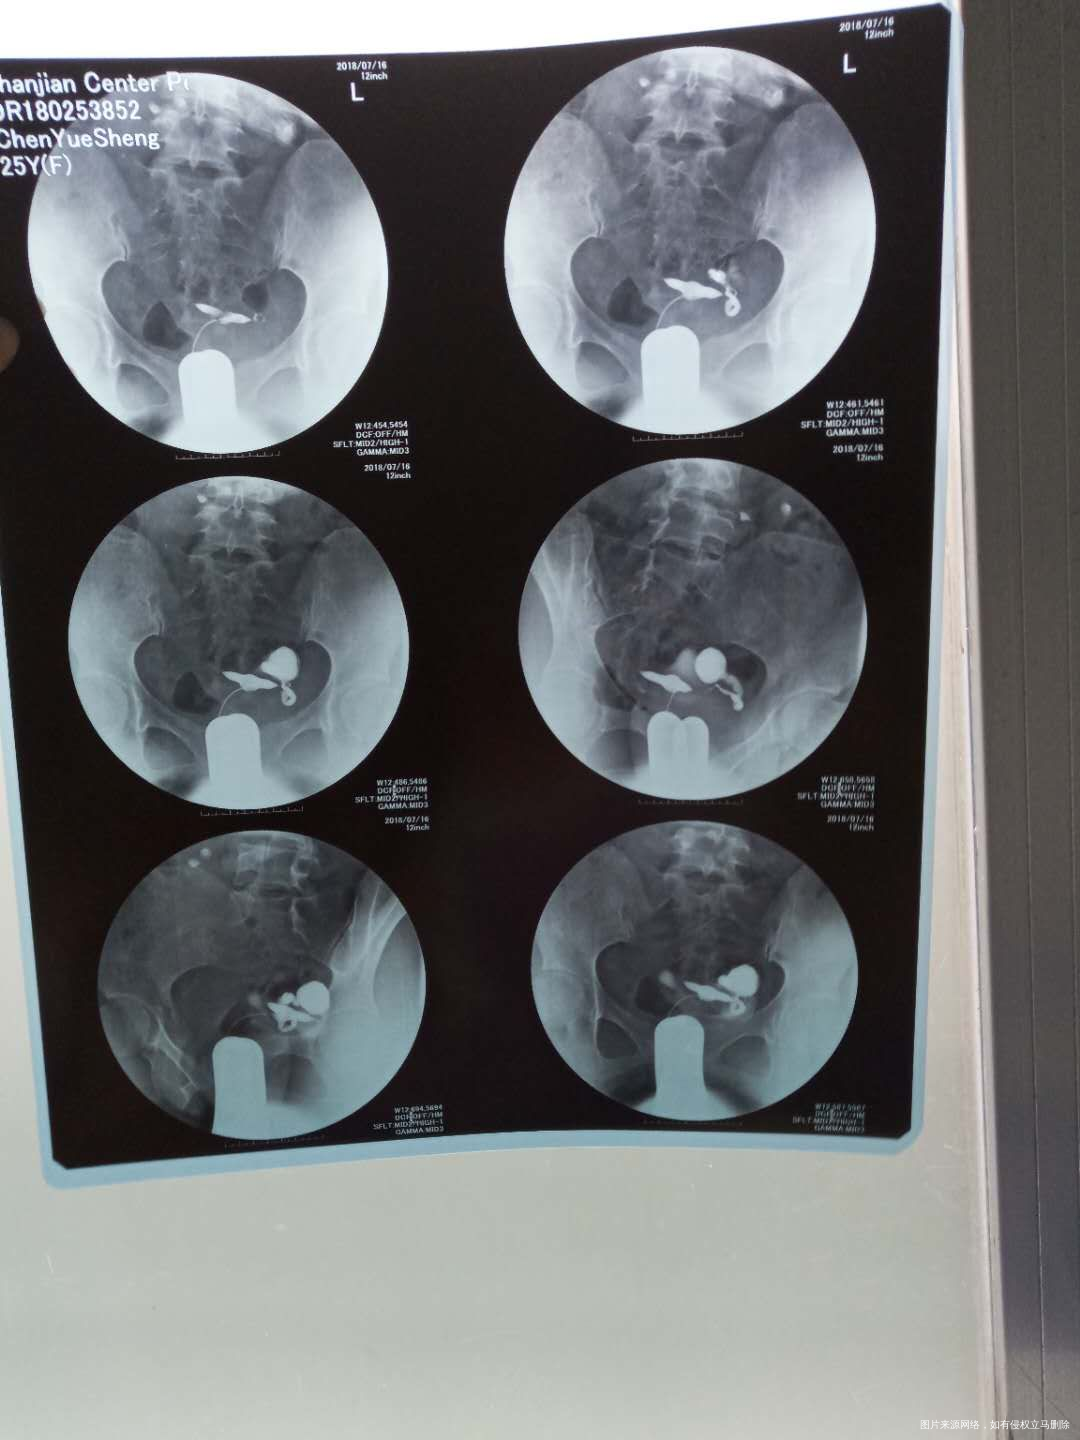

你好,根据你的描述具体建议如下:1 输卵管堵塞,如果备孕的话就会有宫外孕的可能或是不孕的。至于之后会不会加重,这是不好定论的,如果有炎症会刺激盆腔周围组织,造成盆腔炎,引起你的不舒服。 2 目前最好积极治病为主,可以中西医结合治疗。中医中成药加中药灌肠理疗的,西医如果需要手术最好及时治疗。具体根据你的情况再定。3 祝健康。如果我的建议对您有帮助,请记得选择点击采纳哦